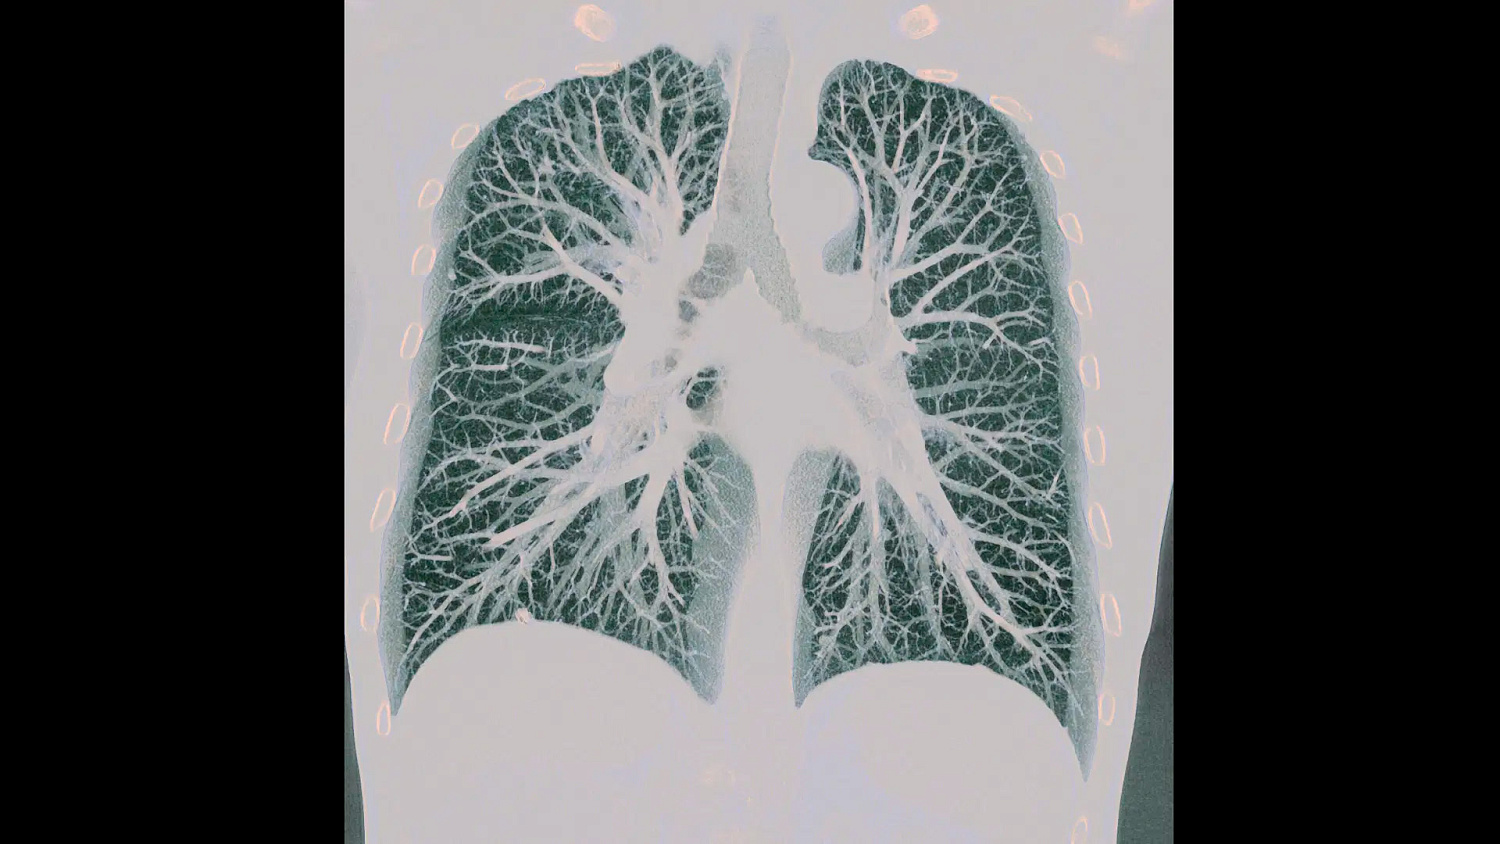

В основе NAEOTOM Alpha ® лежит радикально новый детектор. Детектор QuantaMax напрямую преобразует рентгеновские лучи в электрический сигнал, который затем используется для создания изображения. Измеряется энергия каждого рентгеновского луча, поэтому спектральная информация доступна для каждого сканирования, а изображения получаются контрастными и с высоким пространственным разрешением при той же дозе. Сочетание высокого пространственного разрешения детектора подсчета фотонов QuantaMax с временным разрешением двойного источника позволяет визуализировать мелкие детали для повышения достоверности диагностики.

Сканирование сердца возможно при толщине среза до 0,2 мм. В сочетании с превосходным временным разрешением 66 мс и низким показателем дозы сканирования теперь позволяет выявить впечатляющие детали коронарных сосудов.

QuantaMax, первый детектор фотонов, преодолевает ограничения традиционных детекторов КТ, предоставляя данные с высоким пространственным разрешением, без электронного шума и с улучшенным соотношением контраст/шум.

Рентгеновская трубка Vectron обеспечивает высокое качество изображения даже для пациентов с высоким ИМТ. Микрофокальное пятно (0,4 x 0,5 мм) позволяет использовать высокое пространственное разрешение детекторов QuantaMax.

Уникальная технология Dual Source обеспечивает собственное временное разрешение 66 мс и скорость сканирования до 74 см/с, что позволяет решать даже самые сложные задачи визуализации.